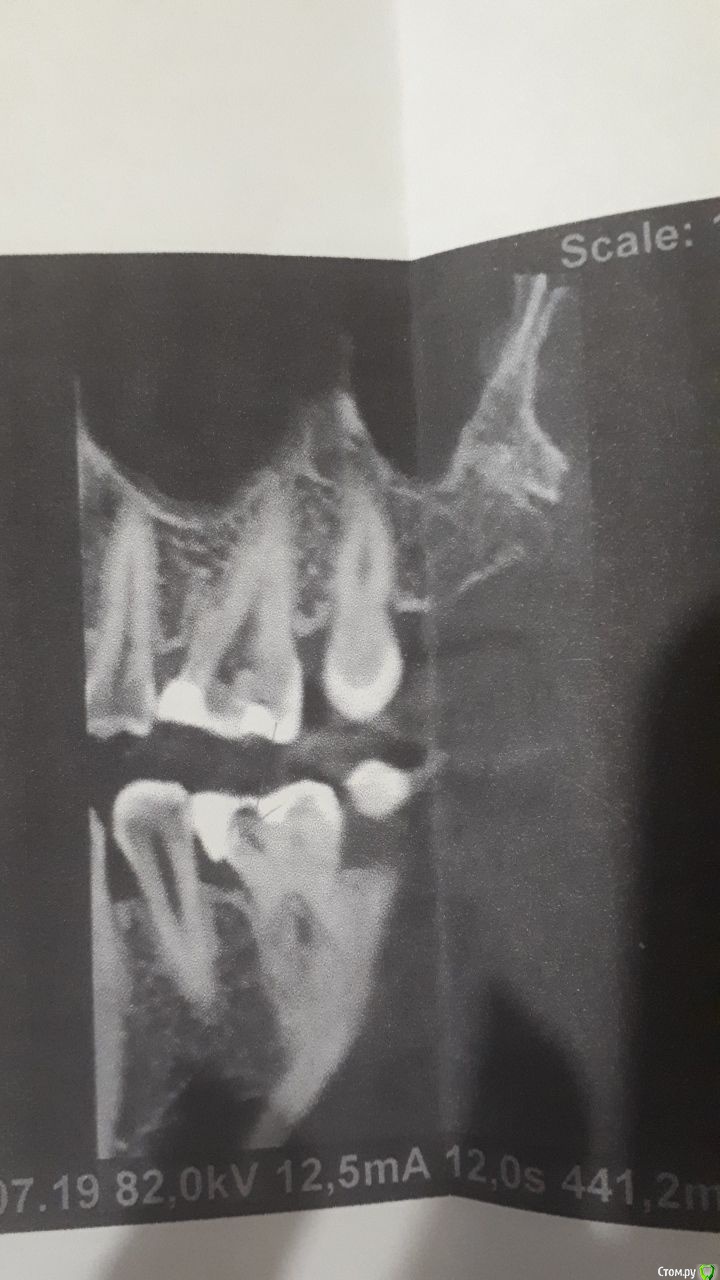

Яковлева Ксения Опубликовано 28 июля, 2019 Поделиться Опубликовано 28 июля, 2019 (изменено) Здравствуйте, уважаемые врачи! 3 недели назад мне запломбировали глубокий кариес в 6 и 7 нижних зубах с правой стороны. До этого эти зубы не беспокоили и не болели. И вот уже 3 недели меня беспокоют ноющие боли. Болит как в течение дня, так и вечером. Когда ем, то твердую пищу больно пережевывать этой стороной, Но болит терпимо. Стоматолог, который пломбировал, считает что так реагирует именно 7 зуб. Он также чувствителен на холодную пищу, на горячее не реагирует. Пломбу уже дважды подпиливали по прикусу, покрывали специальным составом для снижения чувствительности. Я также принимала нимесил в течение 5 дней по рекомендации врача для снижения боли и чистила зубы Сендодином. По рентгену стоматолог сказал, что все хорошо, но если будет и дальше так зуб беспокоить, то стоит его депульпировать (рентген прилагаю). 27.07.2019 я пошла в частную поликлинику, где мне сделали прицельную компьютерную томографию, которая показала, что пломбы как бы не плотно прилегают к зубу. Стоматолог в частной клинике предложил перелечить пломбы. После приема вечером правая сторона разболелась сама по себе, отдавая то в верхнюю челюсть, то под нижнюю челюсть, то в область уха. Болел где-то с 23:30 до 01:30 ночи. Имеет ли смысл перелечивать пломбы на причинных зубах или это пульпит и стоит просто депульпировать 7 зуб? И если перелечивать, не рассверлят ли мне еще глубже полости когда будут снимать пломбы и не приведет ли это к пульпиту? Буду очень признательна вам за консультацию. Фотографии проекций КТ прилагаю. Стрелочками карандашом показаны проблемные места на зубах. Изменено 28 июля, 2019 пользователем Яковлева Ксения Ссылка на комментарий